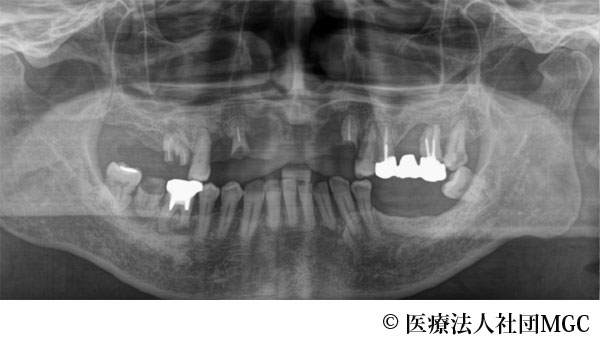

【症例4】上下All-on-4(オールオンフォー)

- 治療前

- 治療後

- 治療名

- 上下All-on-4(オールオンフォー)

- 費用

- 5,888,300円(税込)

- 期間

- 5ヵ月

歯の汚れが気になるのと、奥歯で噛めないとお困りでご来院されました。

ご相談の結果、患者様の生活の質(QOL)を向上させ、しっかり噛め、審美的にも重視した、上下All-on-4(オールオンフォー)を行いました。

機能性、審美性ともに改善し、満足していただけました。